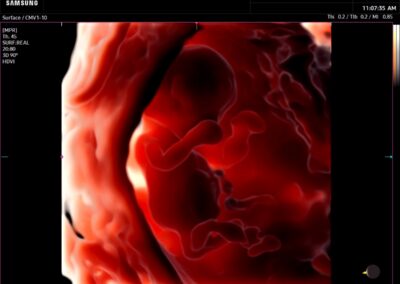

Procedural Services

- Amniocentesis